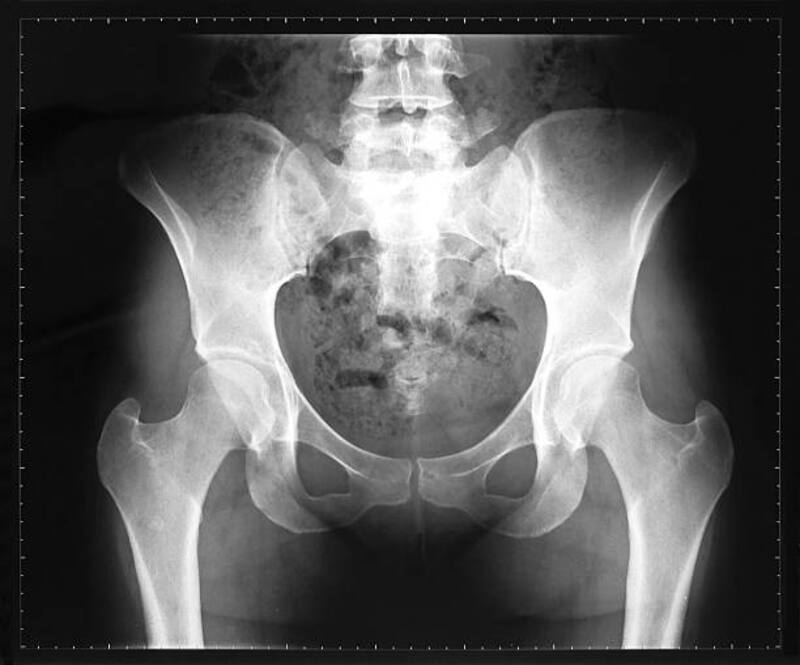

Se ha observado que los músculos de la cola de nuestros ancestros se transformaron en una estructura de soporte importante a medida que los humanos comenzaron a caminar erguidos hace millones de años.